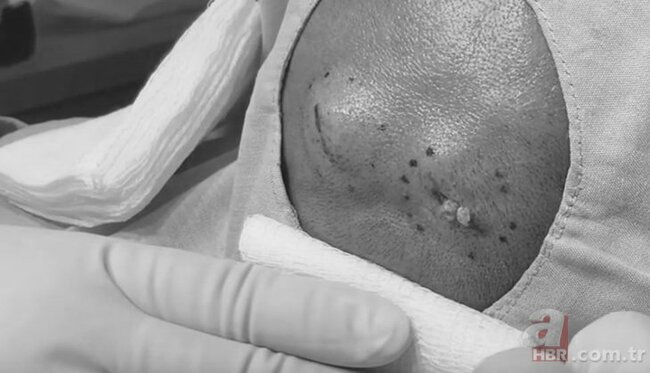

Başında yaranan şiş səbəbindən narahatlıq keçirən bir şəxs həkimə müraciət edib.

BiG.AZ xarici mətbuata istinadən xəbər verir ki, həkim müayinəsindən sonra həmin şəxs əməliyyata alınıb. Əməliyyat zamanı ortaya çıxan görüntülər isə hamını təəccübləndirib.

Belə ki, həkimlər şişi yarıb, bu zaman şişdən ağ rəngli çirk axmağa başlayıb. Əməliyyat nəticəsində həmin şiş təmizlənərək götürülüb.